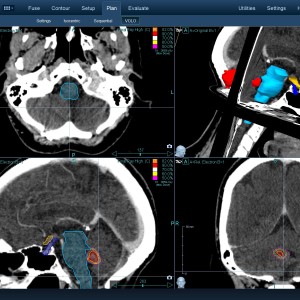

Στις παρακάτω φωτογραφίες θα δείτε παραδείγματα πλάνων θεραπείας καρκινικών όγκων με CyberKnife. Παρατηρήστε πόσο κοντά στους υγιείς ιστούς βρίσκονται οι καρκινικοί όγκοι που χρειάζεται να ακτινοβοληθούν. Μόνο με το CyberKnife και το προσωπικό πλάνο θεραπείας, μπορούν να ακτινοβοληθούν οι όγκοι χωρίς να πληγούν οι παρακείμενοι υγιείς ιστοί.

Μόνο με το CyberKnife και την κατάλληλη σχεδίαση της θεραπείας από έμπειρο νευροχειρουργό, μπορεί να ακτινοβοληθούν οι όγκοι χωρίς να επηρεαστούν από την ακτινοβολία οι υγιείς ιστοί. Αυτό εξασφαλίζει τη μέγιστη δυνατή απόδοση της ακτινοχειρουργικής θεραπείας των όγκων.

Με κόκκινο χρώμα περιγράφεται η περιοχή του όγκου.

Με μπλε, κίτρινο και πράσινο χρώμα περιγράφονται οι υγιείς ιστοί που δεν πρέπει να ακτινοβοληθούν.

Παρατηρήστε πόσο κοντά βρίσκεται ο όγκος με τους υγιείς ιστούς.

Παρατηρήστε τις πάρα πολλές δέσμες του CynerKnife που ακτινοβολούν τους όγκους από διαφορετικές γωνίες ώστε να μην προσβληθούν από την ακτινοβολία οι υγιείς ιστούς.